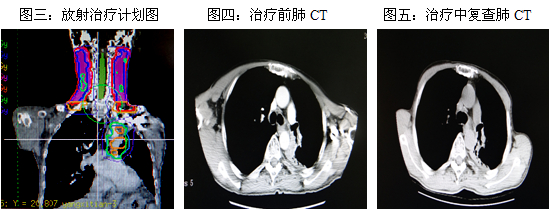

三、利用调强技术治疗一例双重癌病例分享

病例介绍:杨某,因声音嘶哑8个月,咽痛伴吞咽加重3个月入院。查体:浅表淋巴结未触及明显肿大。听诊呼吸音清晰,未闻及干湿?音。PS评分:1分。我院内窥镜检查提示:会厌变形,舌面肿胀,喉面见巨大肿物,向下侵犯双侧室带及右侧声带。右侧披裂及声带固定。左侧声带尚光滑,运动尚可。病理检查结果:(会厌)鳞状细胞癌。肺CT检查提示:肺癌术后,左上纵膈旁团块样软组织密度影,诊断术后复发。拟行支气管镜但因喉腔肿物导致局部气道狭窄,支气管镜无法到达,故未行该检查。余各项检查未见明显异常。

既往史:2010年11月因左肺上叶癌在吉林市某医院行左肺上叶切除术。术后病理:鳞状细胞癌。术后行胸部放射治疗(60Gy/30F),未行化疗。

临床诊断:左肺上叶癌术后、放疗后复发(rT2N0M0 Ⅰb期),喉癌(声门上型 CT3N0M0 III期)。

放疗计划设计:实施肺部复发病灶、喉及其淋巴结引流区一个联合野的调强放疗。现放疗15次,症状改善,复查喉镜:喉病变放疗中好转。肺部CT提示:左上纵膈旁团块样软组织密度影,病变范围较前变小 。

讨论:该患此次入院拟行喉部肿物切除术,但因术前检查发现肺部病灶复发,故采用放射治疗手段。这是一个复杂的病例,治疗难点是:1.两处不规则病变,如何设定两个照射靶区通过一个联合野形式同时进行有效治疗;2.两个靶区要给予不同的照射剂量(肺部靶区二次照射);3.危及器官的受量要求不同的剂量限制;4.照射区剂量分布要均匀。我们通过调强技术得以实现,既使病变区得到高剂量的照射,又保护周围正常组织,治疗效果好,体现了调强放射治疗的优势。同时也缩短了治疗时间,为患者节省了治疗费用。目前患者仍在治疗中,故有待治疗结束后进一步随诊评估。